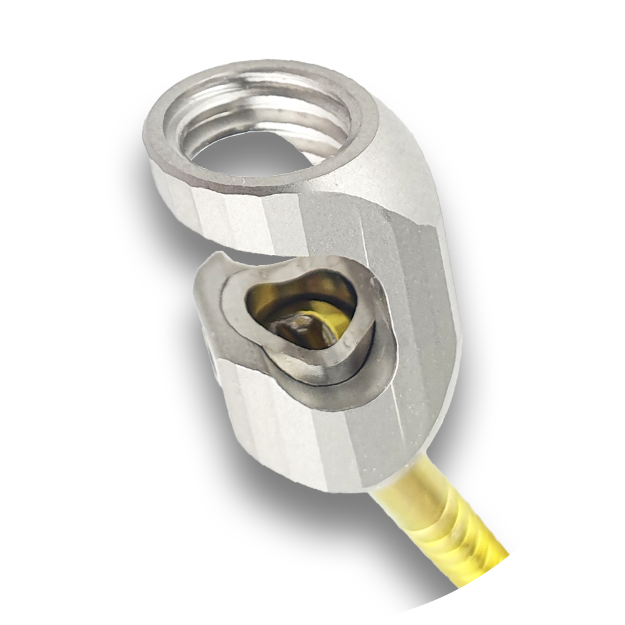

Asymmetric Screw Head for Anatomical Integration

The asymmetric tulip head adapts to the natural contour of the vertebrae, creating a secure bone-comforting fit. Unlike symmetrical designs, this geometry reduces micro-motion at the bone-implant interface, which in turn minimizes soft tissue irritation.

Variable Polyaxial Angulation for Surgical Flexibility

The screw heads allow controlled polyaxial angulation, giving surgeons the ability to fine-tune screw alighnment and rod placement even in anatomically challenging or distorted spinal regions, making implantation safer and more precise.

High Load-Bearing Capacity with Fatneck Design

The specially engineered Fatneck screw design improves stability under repetitive loading and enhances the construct´s resistance to mechanical failure, making LeiPED particularly suited to larger or more active canine patients where higher forces act on the stabilization system.